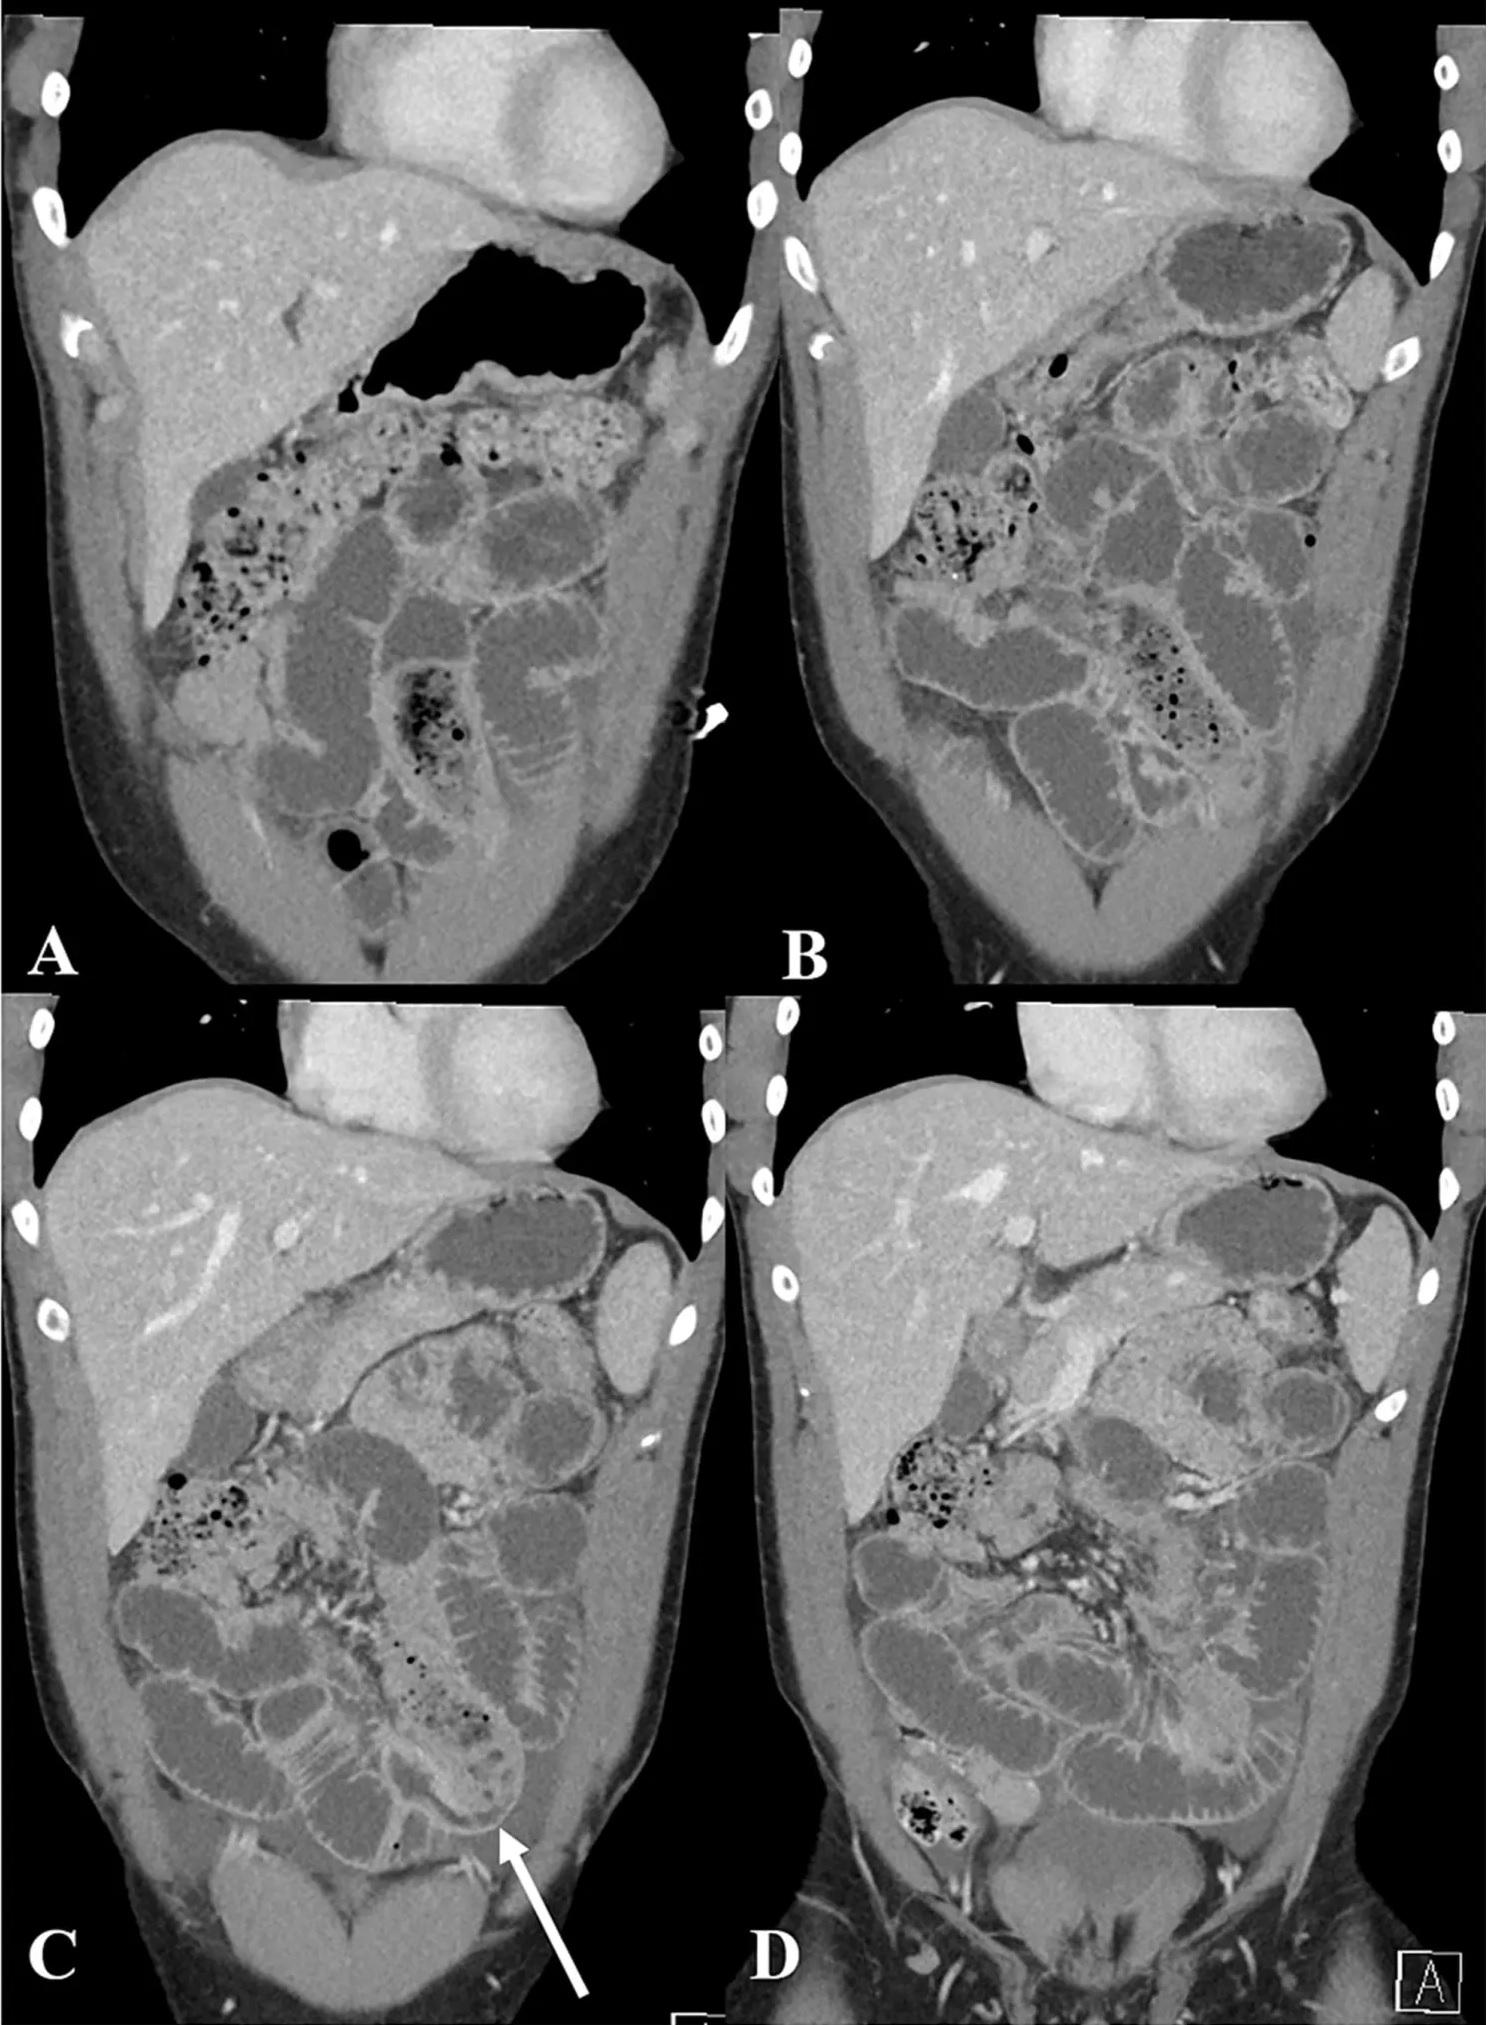

「安全套香蕉」塞在男子的腸道(右圖紅圈示)。(互聯網)

醫生替男子進行電腦掃描檢查後發現,其小腸內有長條狀異物,且嚴重阻塞腸道。醫生隨後動手術將異物取出,可見安全套內的香蕉已發黑,且看不出原型。

男子腸道的電腦掃描影像。(互聯網)